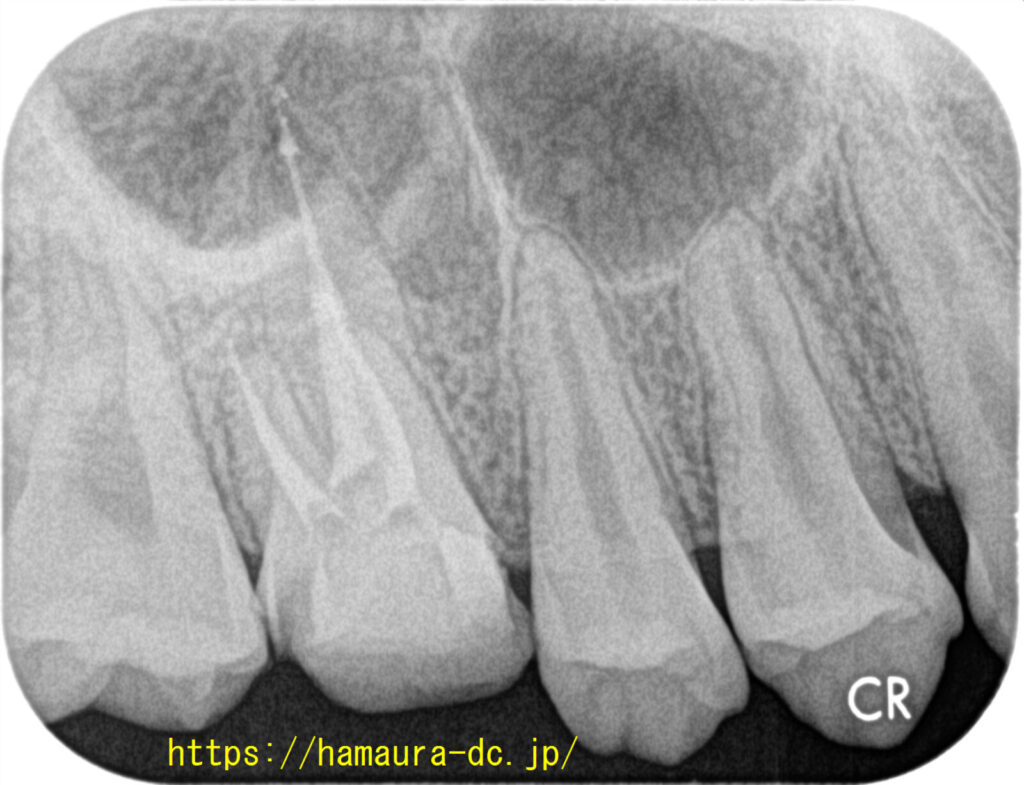

金属修復物(クラウン・コア)を除去し、過去の封鎖材(ガッタパーチャポイント)を除去しました。

また、マイクロスコープの活用、次亜塩素酸ナトリウムおよびEDTAの交互洗浄など、アメリカ標準の根管治療のステップを踏み、

バイオセラミック系シーラーを用いたシングルコーンテクニックで根管充填を行いました。

根尖の外に、シーラーがわずかに漏出していますが、徐々に吸収されていく材料です。